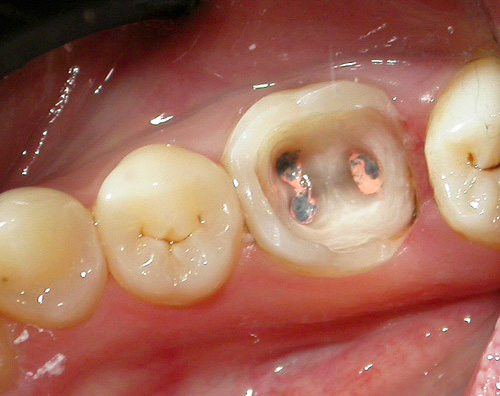

E in questa foto - carie profonde, che già minaccia di svilupparsi in pulpite:

Con la carie profonda, come suggerisce il nome, gli strati profondi di dentina sono interessati fino alle aree vicino alla polpa. Se la polpa stessa è interessata, la pulite inizia con dolore acuto e il rischio di infiammazione parodontale.

E qui ci sono denti con profonde cavità cariate sulle superfici masticatorie: